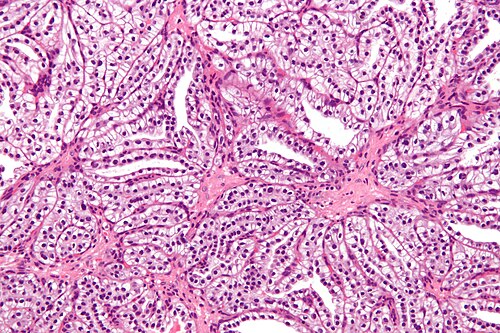

62 year old woman, renal mass.

High magnification. H&E stain.